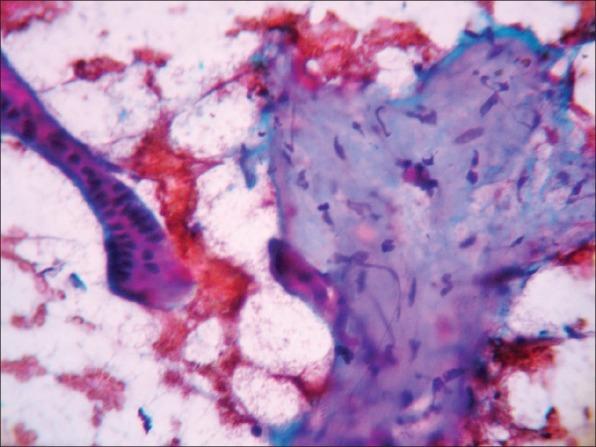

Sterocleidomastoid tumor of infancy (SCMI), also known as fibromatosis colli of infancy, is a benign, self limiting disease of new born characterised by its classical history and clinical presentation of firm to hard fusiform mass in the lower and middle portion of sternocleidomastoid. SCMI often appears during early perinatal period between second to fourth weeks of life. A well recognized association between SCMI and primiparous birth, breech presentation, prolonged difficult labor and forceps deliveries is found. Cytology shows spindle shaped mature fibroblastic cells scattered singly along with degenerated and multinucleated giant muscle cells in a clean background. It is important to differentiate this lesion from different forms of infantile fibromatosis. Fine-needle aspiration cytology (FNAC), as a time saving, rapid and reliable diagnostic procedure, has got bigger role to play in reassurance of anxious parents, guiding for conservative management and avoiding surgery.

婴儿胸锁乳突肌肿瘤(SCMI),也称为婴儿颈部纤维瘤病,是一种新生儿的良性自限性疾病,其典型病史和临床表现为胸锁乳突肌中下部分出现质地坚硬至硬的梭形肿块。SCMI通常出现在围产期早期,即出生后第二至第四周。人们发现SCMI与初产、臀位产、产程延长困难和产钳分娩之间存在明确的关联。细胞学检查显示梭形成熟成纤维细胞单独散在分布,背景清晰,伴有退化的多核巨肌细胞。将此病变与不同形式的婴儿纤维瘤病进行鉴别很重要。细针穿刺细胞学检查(FNAC)作为一种省时、快速且可靠的诊断方法,在安抚焦虑的父母、指导保守治疗和避免手术方面发挥着更大的作用。